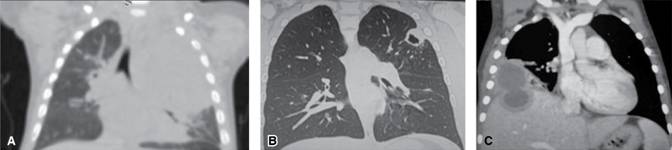

Ppt Hallazgos Radiologicos En La Mucormicosis M Larios A Soley D Villa S Rosa C Delgado T Sempere Hospital Univ Powerpoint Presentation Id 964164

Hallazgos Radiolgicos En La Mucormicosis M Larios A